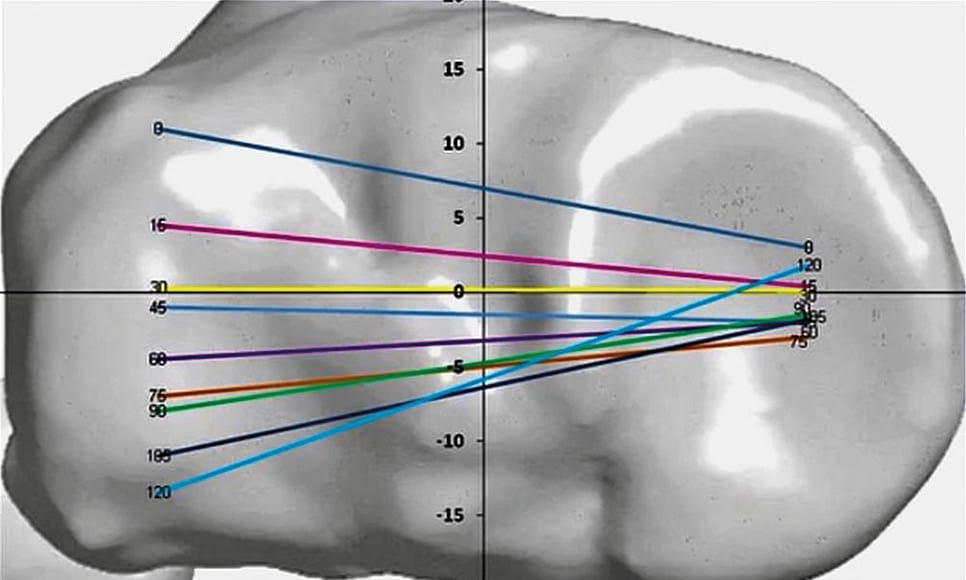

Personalized alignment for CPAK 1, 2 and 4

The ongoing debate between personalized and one-fits-all approaches continues to evolve with emerging evidence. Different response patterns has been described among different Coronal Plane Alignment of the Knee (CPAK) phenotypes, identifying types 1 and 4 classes as optimal candidates for personalized alignment strategies achieving better functional and performance outcomes [30] MacDessi SJ, Griffiths-Jones W, Harris IA, Bellemans J, Chen DB. Coronal Plane Alignment of the Knee (CPAK) classification. Bone Joint J 2021;103-B:329–37. https://doi.org/10.1302/0301-620X.103B2.BJJ-2020-1050.R1..

Individual joint and surgeon experience responses to complex ligamentous balancing procedures may vary, producing inconsistent results with mechanical alignment methods [2] Rak D, Klann L, Heinz T, Anderson P, Stratos I, Nedopil AJ, et al. Influence of Mechanical Alignment on Functional Knee Phenotypes and Clinical Outcomes in Primary TKA: A 1-Year Prospective Analysis. J Pers Med 2023;13:778. https://doi.org/10.3390/jpm13050778.. Mechanical alignment in varus morphotypes necessitates trapezoidal resection gaps requiring soft tissue releases which leading to outcomes dependent on surgeon skill and unpredictable tissue responses. Conversely, performing preserving bone cuts that maintain the native deformity, completely or partially through morphotype-specific alignment, avoids the inherent uncertainties following complex release procedures and achieving knees with improved lacity gaps and soft tissue laxity patterns [31] Franceschetti E, Campi S, Giurazza G, Tanzilli A, Gregori P, Laudisio A, et al. Mechanically aligned total knee arthroplasty does not yield uniform outcomes across all coronal plane alignment of the knee (CPAK) phenotypes. Knee Surg Sports Traumatol Arthrosc 2024;32:3261–71. https://doi.org/10.1002/ksa.12349.. This approach can improve clinical outcomes by avoiding extensive soft tissue manipulation.

CPAK type 2 patients, despite exhibiting very little or no deviation from neutral alignment, still benefit from personalized strategies, indicating that following the native joint line orientation provides clinical advantages even among neutrally aligned limbs [32] Yang H, Park C, Cheon J, Hwang J, Seon J. Comparison of Outcomes Between Functionally and Mechanically Aligned Total Knee Arthroplasty: Analysis of Parallelism to the Ground and Weight-Bearing Position of the Knee Using Hip-to-Calcaneus Radiographs. J Pers Med 2025;15:91. https://doi.org/10.3390/jpm15030091.. For neutral alignment patterns, particularly CPAK type 5 patients, personalized approaches may not demonstrate significant differences compared to mechanical alignment techniques.

Evidence remains insufficient among valgus morphotypes and severe varus deformities - severe CPAK types 1 and 4 - where neutral restoration may surpass the compensatory capabilities of personalized approaches among valgus and very high degrees of varus deformities or distortion.